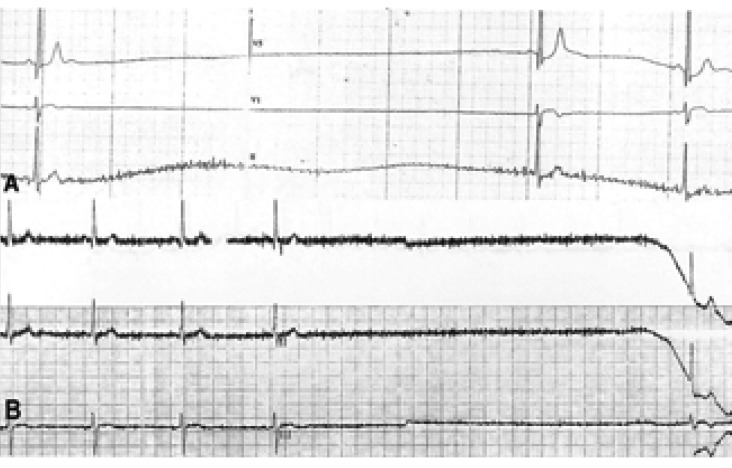

A 59-year-old male was referred to hospital for the evaluation of about four episodes of syncope which he had experienced for 1 year. The first episode occurred with a loss of consciousness for 5 minutes following eating foods with feeling obstruction in the esophagus. No specific kinds or forms of foods had been associated with the symptom. He had experienced syncopal episodes usually right after eating, but sometimes while eating foods. The patient had been in good health except for having about ten episodes of an obstructive feeling while eating for 3 years. The result of an esophagogastroscopy conducted 1 year ago had been normal. Physical examination results showed no abnormality. The laboratory FT4: 26.445 pmol/L, TSH receptor antibody 30.5%). The blood count and liver function tests were normal. An electrocardiography showed sinus bradycardia (57 beats per minutes). A chest X-ray showed a compression fracture at the lower thoracic spine. A thyroid scan showed no demonstrable abnormal finding. The Holter monitoring test could not be done for refusal of patient and rarity of the symptoms. Inflation of the balloon in the lower esophagus and gastroesophageal junction that was at the 9th thoracic spine level resulted in junctional rhythm (32~36 beats per minutes) with lightheadedness (Figure 3, Figure 4). However, an atropine pretreatment blocked this response (Figure 3C). A syncopal episode was considered to occur with eating a bolus of food in a hurry; thus, he was treated by changing his eating habits for syncope and given propylthiouracil for Graves' disease.

(A) Esophageal balloon inflation at the T7 level of the esophagus made a sinus pause (3.08 seconds) and marked bradycardia. (Case 2) B. Esophageal balloon inflation at the T9 level of the esophagus initiated a junctional rhythm. C. Esophageal balloon inflation at the T9 level of the esophagus after atropine 1mg IV blocked the reflex.

T: thoracic vertebra